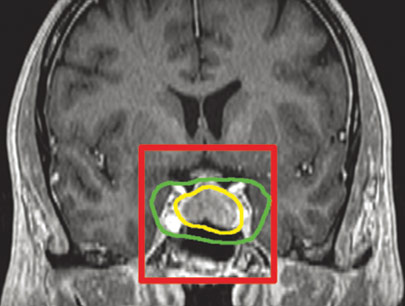

(Wanita, 48 tahun)

Diagnosis: Tumor Sphenoid Wing 1/3 Medial Curiga Meningioma

Sebelum Gamma Knife

• Nyeri Kepala

• Buta mata kiri (tidak bisa melihat cahaya)

• Penonjolan mata kiri

3 bulan Setelah Gamma Knife

• Kebutaan menetap

• Penonjolan mata kiri berkurang

Volume Tumor: 3.45 cm3

Volume Tumor: 2.3 cm3